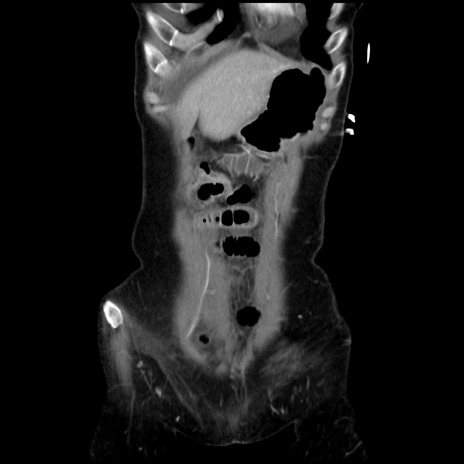

矢状断像